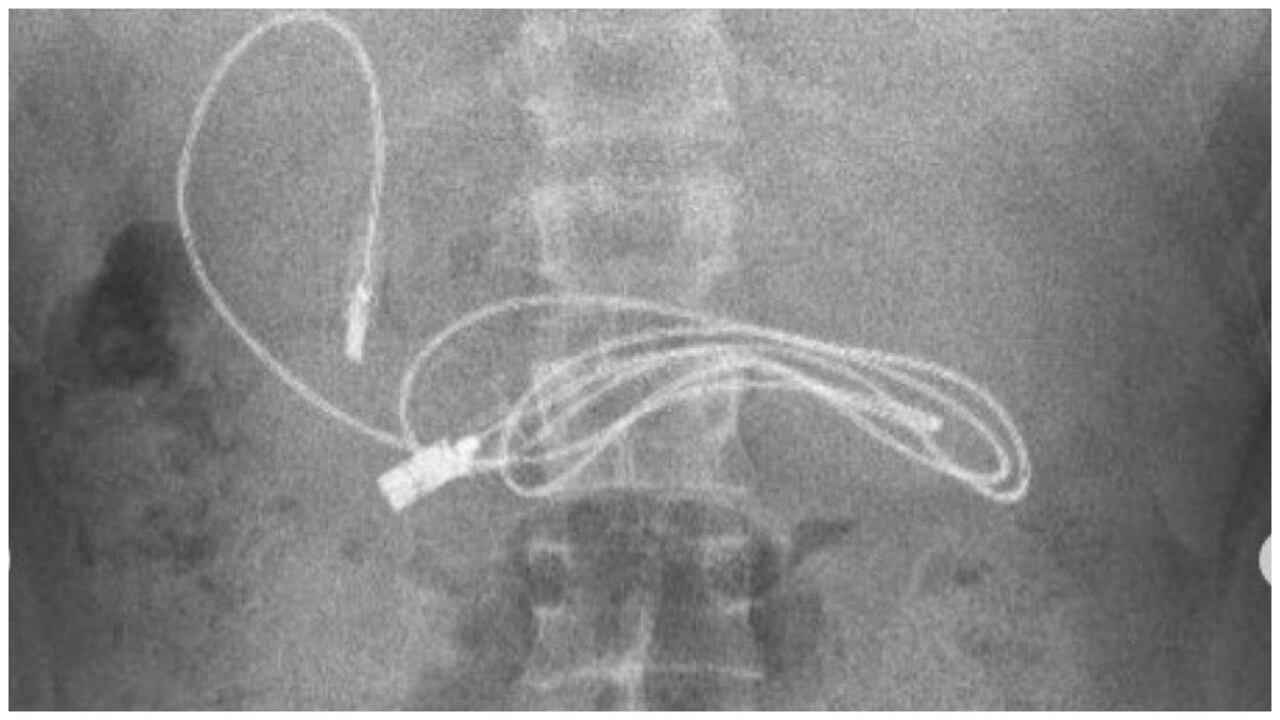

El gastroenterólogo pediátrico Yasar Dogan fue quien se encargó de la situación. Además, por medio de sus redes sociales compartió las impresionantes imágenes que comprueban la situación vivida por su paciente.

El profesional de la salud tomó la decisión de realzar un procedimiento con endoscopio para poder a través de la boca y el conducto gástrico llegar hasta donde se encontraba alojado el cargador de celular. Cuando por fin se logró hacer contacto con el objeto, el doctor Dogan se percató de que también había una banda elástica para cabello junto al cargador.

“Obviamente, tuvimos dificultades para quitar el cable, ya que un extremo del cable había pasado al intestino delgado (...) Después de que el procedimiento concluyó con éxito, el paciente fue enviado a casa con buena salud”, explicó el doctor Yasar Dogan.